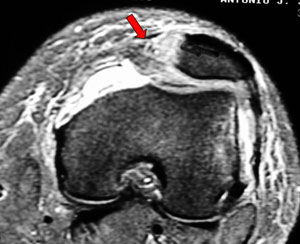

Deslocamento Patelar + Lesão do Retináculo

![]() |